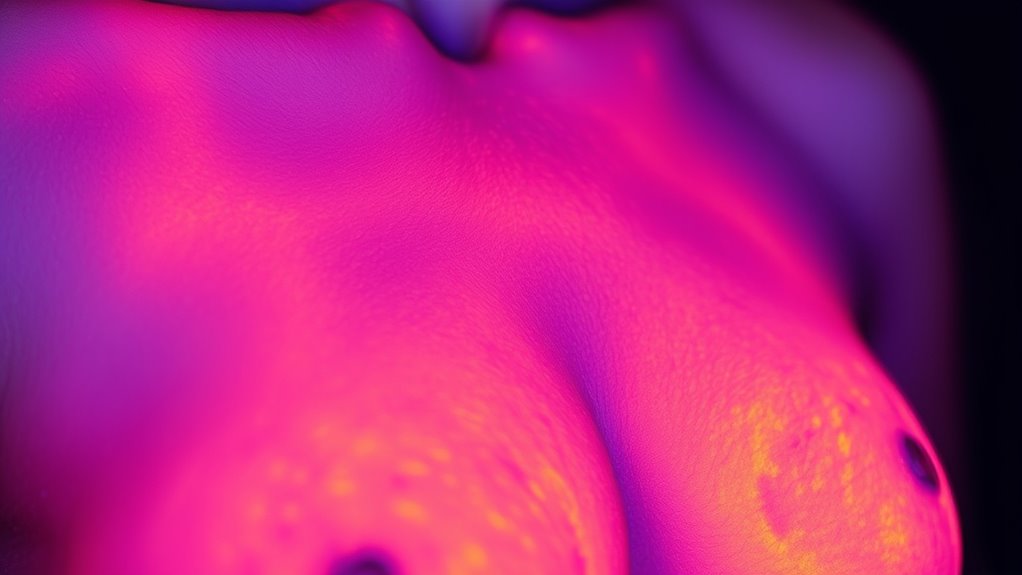

Die Thermografie funktioniert durch die Verwendung von Infrarotkameras, um Oberflächentemperaturveränderungen auf der Haut der Brust zu erkennen. Diese Wärmebilder zeigen Bereiche mit vermehrtem Blutfluss oder erhöhtem Stoffwechsel, was auf zugrunde liegende Probleme hindeuten kann. Da sie jedoch nur die Oberflächenwärme misst, kann die Thermografie die innere Struktur des Brustgewebes nicht sichtbar machen. Diese Einschränkung bedeutet, dass sie keine kleinen Tumore oder detaillierte Anomalien im Inneren der Brust erkennen kann. Zudem können Wärmemuster durch nicht-krebsartige Faktoren wie Entzündungen, Infektionen, hormonelle Veränderungen oder Umwelteinflüsse beeinflusst werden, was zu falsch positiven oder falschen negativen Ergebnissen führen kann. Die Thermografie liefert keine anatomoischen Bilder oder genaue Lokalisierungen von Anomalien, was sie bei der Diagnose von Brustkrebs weniger zuverlässig macht. Ihr oberflächenorientierter Ansatz beschränkt ihre Fähigkeit, durch genauere strukturelle Bildgebung wie Mammographie ersetzt zu werden.